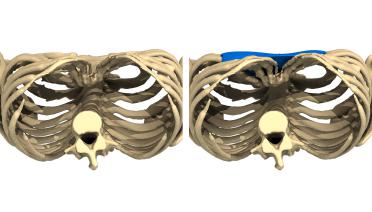

La tecnica di impianto su misura è una tecnica chirurgica minore che consiste nel riempire la concavità creata dal Pectus con un impianto personalizzato. Si tratta di un intervento rapido, a basso rischio, con un risultato immediato e una breve convalescenza.

Tipo 1 : Mediano, profondo e simmetrico,